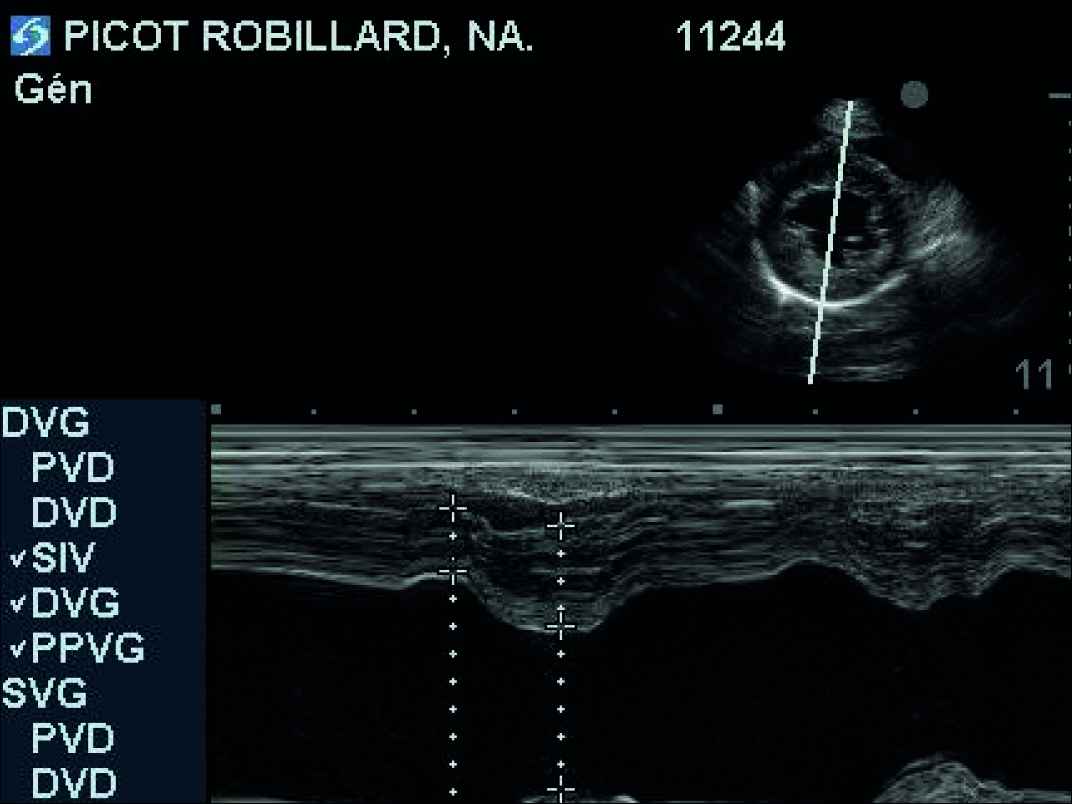

- L'examen échocardiographique révèle une insuffisance de la valve mitrale centrale, peu évoluée, sans aucun remodelage des feuillets mitraux, ni modifications des dimensions de l'atrium gauche et du ventricule gauche (VG normalisé à 1,7 : discrètement au-dessus de la norme) : stade ACVIM B1. La distance point E-Septum est estimée à 10 mm (norme supérieure acceptée : 7 mm). On note donc essentiellement une mauvaise fermeture des feuillets mitraux par agrandissement de l'anneau mitral. Enfin, une petite fuite pulmonaire est visualisée mais sans aucune répercussion sur l'état clinique ou hémodynamique du coeur (cavités droites sans aucun signe de souffrance).

Un suivi clinique et échocardiographique (tableau n° 2, photos n° 1, 2 et 3), électrocardiographique (photo n° 4) et mesure du NT-proBNP (tableau n° 3) sont entrepris sur 12 mois avec une visite à 4 mois (V2), 6 mois (V3) et 12 mois (V4).

Au cours des examens échocardiographiques, une très faible dilatation de l'atrium gauche a été observée (passage d'un rapport OG/Ao de 1 à 1,4). La dilatation du VG ne s'est pas aggravée au cours des 12 mois (42 mm en télédiastole à V1 et V4). On note une amélioration puis une stabilisation de la distance point E-Septum.

La capacité du VG à se contracter reste dans la norme tout au cours de l'étude : pas d'altération de l'inotropisme du VG (fraction de raccourcissement et d'éjection dans les valeurs usuelles).